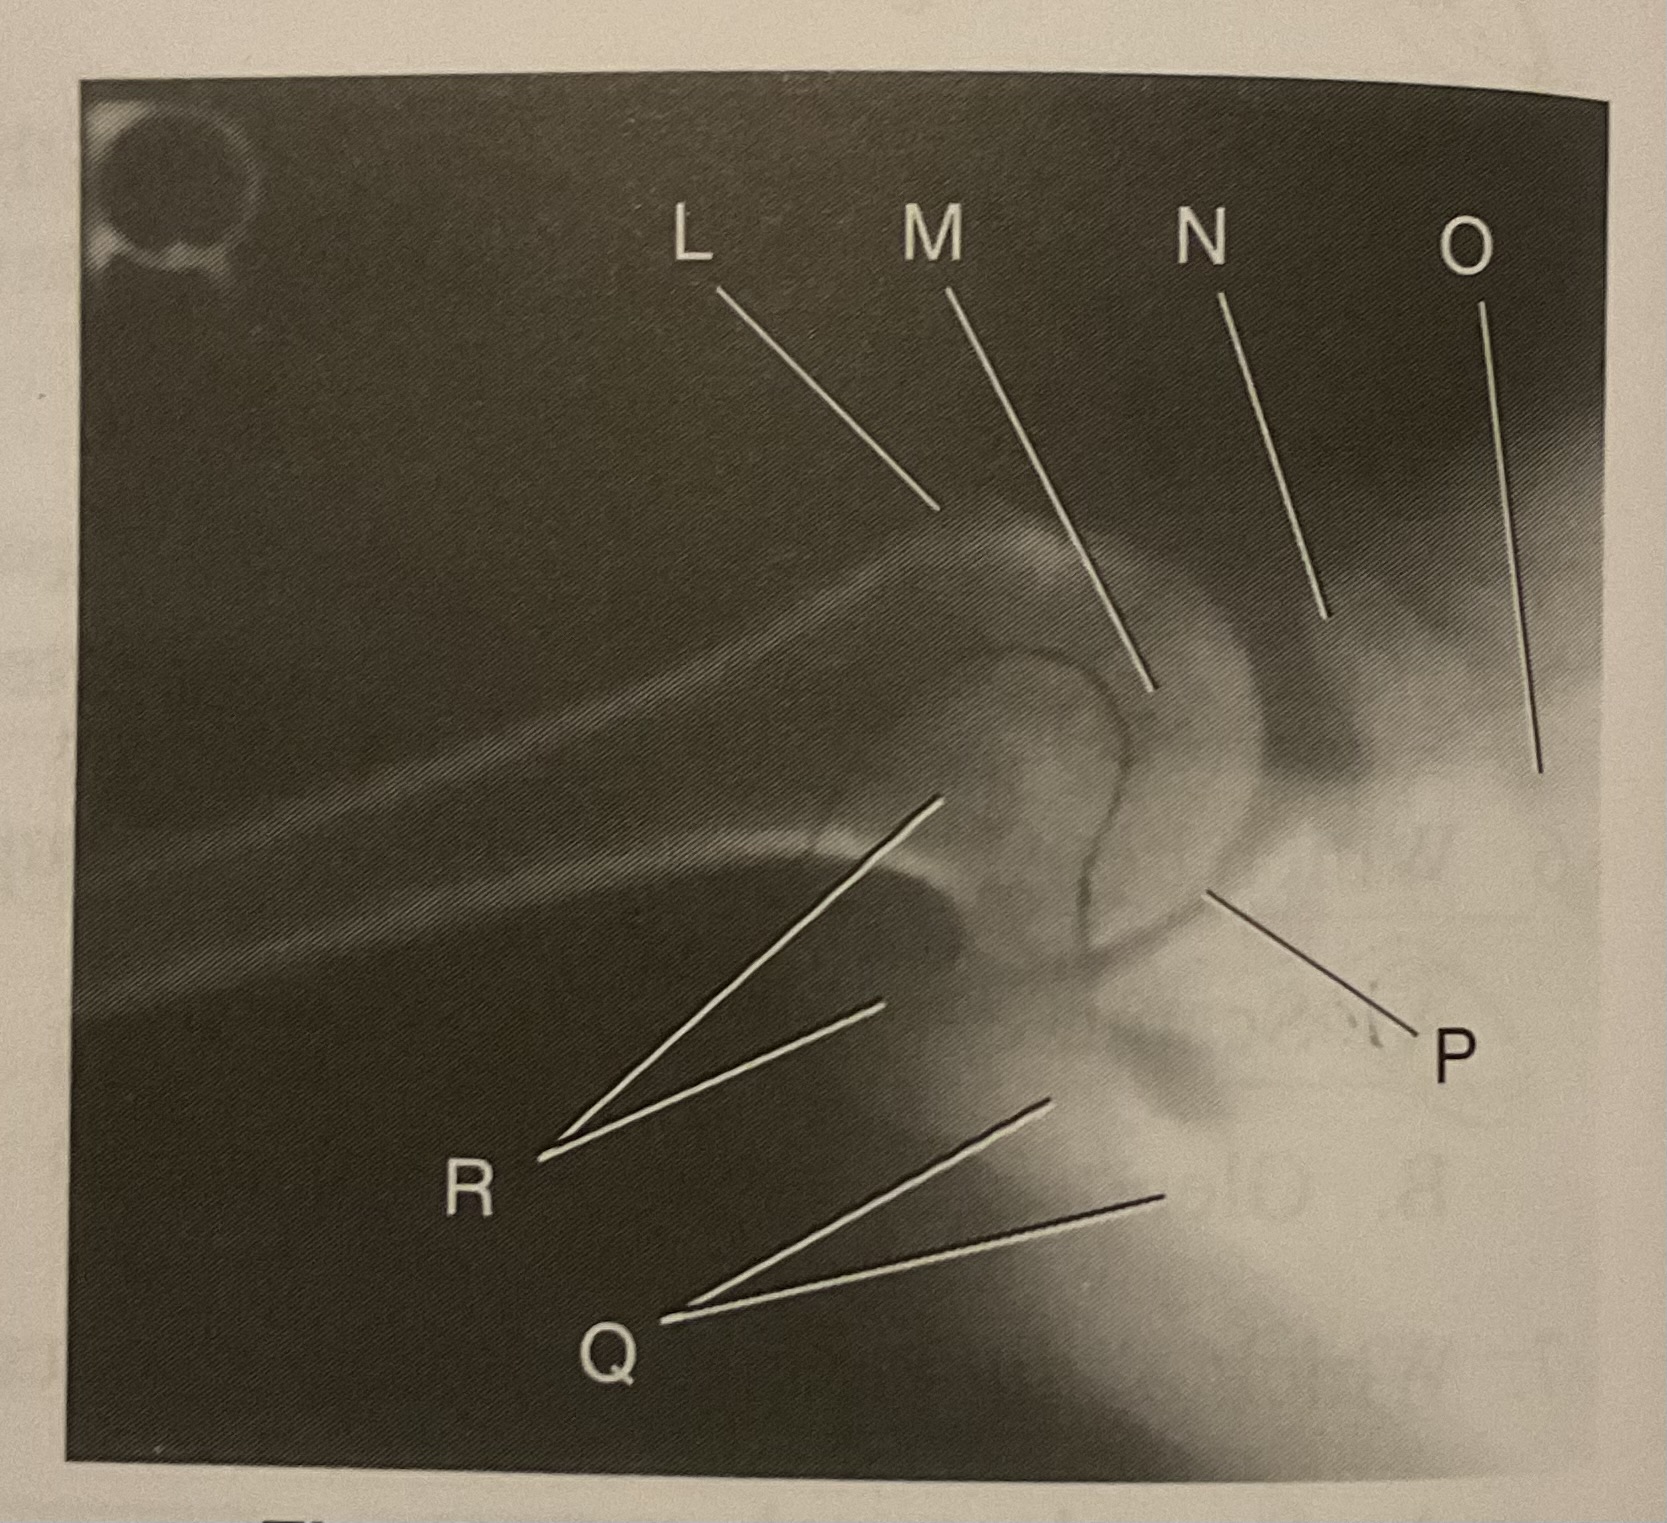

What AP projection does this image represent?

External

L?

Lesser tubercle

M?

Head of humerus

N?

Coracoid process

O?

Clavicle or lateral extremity of clavicle

P?

Glenoid cavity or Scapulohumeral joint

Q?

Spine of scapula

R?

Acromion of scapula

What is the correct term and method for the projection seen in this image?

Inferosuperior axial projection